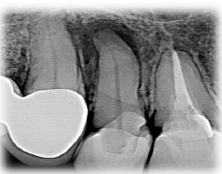

I. O filme precisa conter a totalidade da(s) coroa(s), da(s) raiz(es), e de 2 a 3 mm de tecido ósseo saudável recobrindo o(s) ápice(s) ou a imagem patológica periapical. As radiografias panorâmicas ou oclusais devem ser realizadas quando há a necessidade de avaliação de áreas mais extensas.

II. A(s) imagem(ns) deve(m) ter qualidade suficiente para proporcionar análises acuradas da(s) área(s) e/ou do(s) dente(s) de interesse, devendo conter alongamento ou encurtamento.